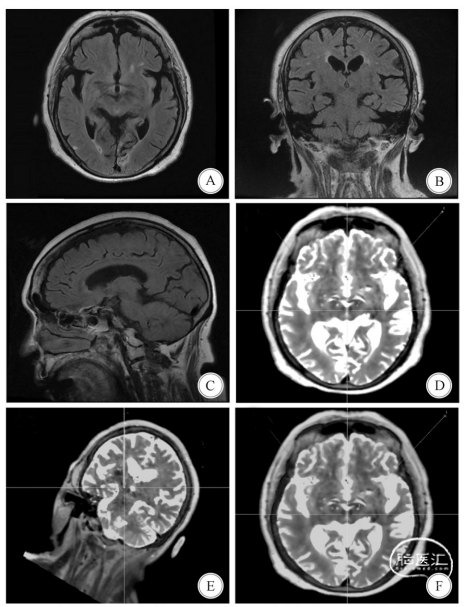

A—C:术前MR,FLAIR轴、冠、矢状位显示多发软化灶,脑萎缩;D:手术计划,靶点左(x:-12.0,Y:-2.0,z:-5.0),右(x:12.0,Y:-2.0,z:-5.0);F:术后融合靶点,显示电极的针道路径;F:术后融合显示左侧偏差0.3mm,11侧偏差0.6mm

图2 病例2患者的影像资料、手术计划和融合后电极位置